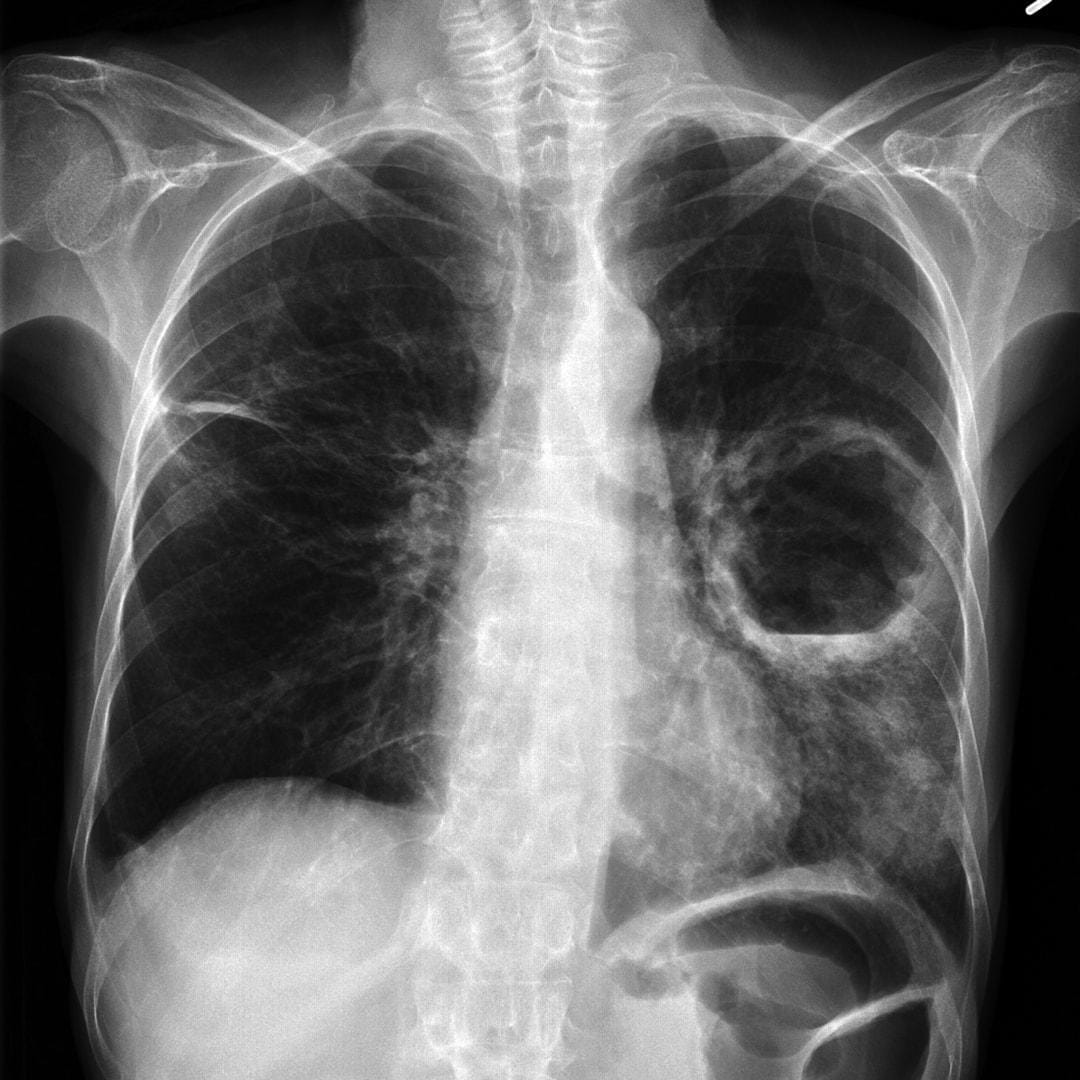

Silicosis is an 'occupational' lung disease. That is, you get it simply by doing your work – in this case by breathing in crystalline silica dust, causing lung inflammation and fibrosis, with no cure.

Workers using power tools to cut, grind or drill the product without adequate masks or cutting it dry rather than wet (with water) can be exposed to extremely high levels of silica dust, which scars the deepest parts of the lungs.